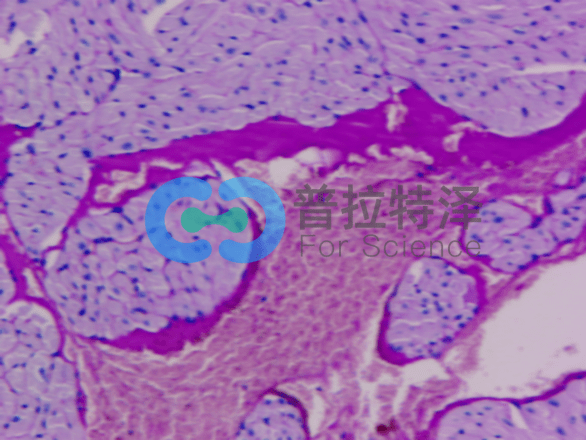

[圖2]

二、細胞類型和結(jié)構(gòu)

PAS染色不僅可以顯示多糖類物質(zhì),還可以揭示細胞的類型和結(jié)構(gòu)。例如,在某些病理狀態(tài)下,某些細胞可能會過度分泌多糖類物質(zhì),導致染色結(jié)果異常。通過觀察這些細胞的形態(tài)和分布,我們可以進一步了解疾病的發(fā)病機制和進展過程。

HE染色

八月瓜果皮PAS染色